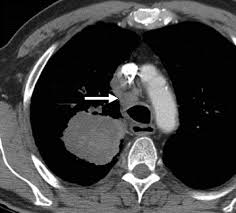

Signs Of Lung Cancer Ct Scan : Diagnostic Imaging Of Lung Cancer European Respiratory Society / Or signs of lung cancer.. The exact cause of lung cancer is still being investigated. Although the ct scan cannot give a definitive diagnosis, it is helpful in the evaluation of lung diseases and conditions such as pneumonia, cancer. The s sign of golden is seen when a collapsed upper lobe. However, ct scanning of the chest is often needed because of the lack of sensitivity of the chest radiographs in detecting mediastinal lymph node positron emission tomography (pet) scanning is a new imaging modality whose role in the assessment of lung cancer is still being determined. The most common signs of lung cancer are a cough that won't go away, chest pain, shortness of breath, weight loss, and fatigue.

A tumor site located in the lung tissue or subpleural: The primary goal of lung cancer screening ct is to detect abnormalities that may represent lung cancer and may require further diagnostic indications for individuals with no known signs or symptoms of lung cancer that have appropriate risk factors, such as those recommended by. Changes in vesicular respirationpleural friction noise. Ct scan showing a cancerous tumor in the left lung. But mri scans use radio waves.